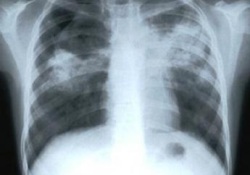

13.02. пошла к доктору. Доктор послушала, ничего не услышала и отправила на рентген. На рентгене выявилась " пневмани, не исключен специфический характер". Выписали больничный,фромилид уно и ГелоМиртол форте от кашля.15.02 сделали КТ, по КТ сказали что не исключают туберкулез, выписали направление к фтизиатру.

Пульмонолог, изучив материал, сказала, что по КТ это точно пневмания, туберкулеза никакого она там не видит. Назначила Таваник на 10дней, Лазолван и через 14дней после окончания приема Таваника сделать повторное КТ.

В проекції верхньої частки правої легені (переважно S3)візуалазується щільне вогнище, розмірами до 12 мм в діаметрі. У медіальній частині вогнища визначається просвітлення правильної округлої форми, вірогідно прсвіт бронха. Перифокально візуалізуються множинні дрібні поліморфні вогнища з нечіткими контурами.

В інших легеневих полях КТ ознак пат уражень легеневох паренхіми вогнищового інфільтративного чи обьємного характеру - не виявлено.

Легеневі корені структурні помітно розширені за рахунок судинного компонента.

Скопичення вільної рідини в порожнечі плеври - не спостерігається.

Середньостіння-розташоване по середній лінії, не розширене. Наявності органічного (зокрема обьємного) пат ураження в проекції переднього , середнього, та заднього його відділів - не спостерігається.

КТ-ознаки лімфоденопатії відсутні.

Вот так если это ТБ я готов лечится(так как у меня маленькая дочь и жена), если нет как узнать что это